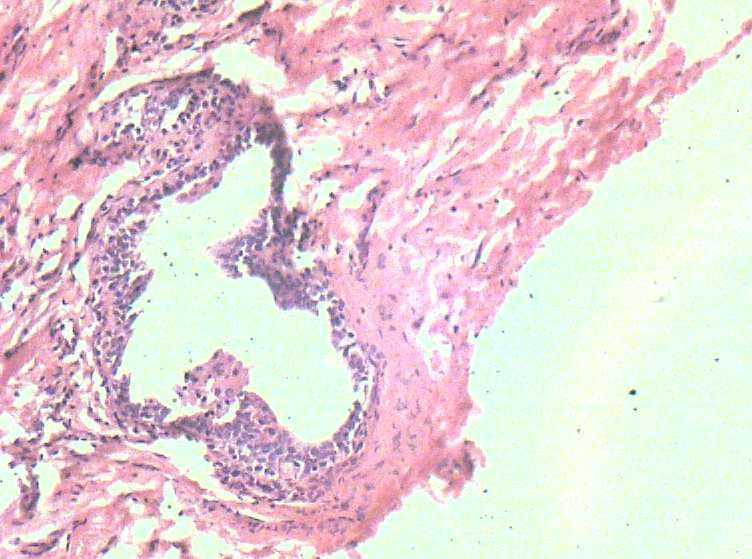

B3774乳腺积乳性包块?

女41岁,左腺包块。肉眼:不整形囊壁样组织,大小2*1.6*0.3CM,壁厚0.1—0.3,未触及结节,未见出血及坏死。

似乎有导管扩张、慢性炎细胞浸润、大汗腺化生、普通型导管增生等病变,没有看到囊壁内衬上皮或囊壁结构。

这例报了 慢性囊性乳腺病。不知可否?

囊性纤维性乳腺病。

纤维性囊性乳腺病

乳腺腺病伴普通型导管增生

报乳腺增生性腺病伴导管上皮不典型增生。

。图12-16可以看到导管上皮异形增生(导管上皮极向紊乱)